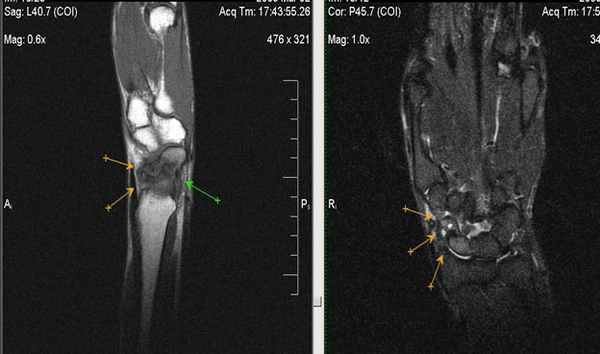

(Слева) Рентгенография левого лучезапястного сустава в ПЗ проекции: повышение плотности полулунной костив. Нет потери высоты и фрагментации. Признаки соответствуют II стадии болезни Кинбека.

(Справа) Фронтальная Т1ВИ МР-И: неоднородный гипоинтенсивный до темного сигнал в полулунной кости. Темный сигнал соответствует склерозу/фиброзу при прогрессировании заболевания. Структурные изменения визуализируются и на других изображениях, что указывают на III стадию болезни Кинбека. (Слева) Рентгенография в ЗП проекции: неоднородный склероз полулунной кости со значительным коллапсом проксимальной суставной поверхности. Несмотря на выраженные изменения, было выполнено укорочение лучевой кости. Операция выполнена для коррекции отрицательного локтелучевого индекса в попытке уменьшения механической нагрузки на деформированную полулунную кость.

(Справа) Рентгенография в ЗП проекции, этот же пациент после лечения по поводу хронического болевого синдрома. Полулунная кость была резицирована и выполнен ограниченный (головчато-крючковидный) остеосинтез. (Слева) Фронтальная Т2ВИ FS МР-И: I стадия болезни Кинбека. Отрицательный локтелучевой индекс. Отек костного мозга в полулунной и головчатой костях. Отек головчатой кости возможен на фоне нарушения осевой механической нагрузки вследствие короткой локтевой кости.

(Справа) Фронтальная T1 ВИ МР-И, этот же пациент: отек костного мозга в полулунной кости. Главная ось нагрузки проходит от лучевой кости к полулунной и головчатой до среднего пальца, ее легко оценить. Нормальная рентгенологическая картина говорит о I стадии маляции полулунной кости.

4. МРТ при остеонекрозе лучезапястного сустава:

• Т1 ВИ: ↓ интенсивности сигнала, в зоне перелома может визуализироваться линия низкого сигнала

• Последовательности, чувствительные к жидкости: изменения сигнала достаточно вариабельны; характерно раннее ↑ сигнала, позднее ↓ сигнала:

о Линия перелома темная или яркая, визуализируется не всегда

• Т1 ВИ С+: недостаток усиления предполагает наличие нежизнеспособных фрагментов:

о Не всегда является специфичной; позже может произойти реваскуляризация

• Распределение изменений сигнала достаточно вариабельно:

о Могут вовлекаться мелкие сегменты или кость целиком, может быть очаговое или диффузное, изменяется между последовательностями

о При вторичном остеонекрозе, визуализируются субхондральные изменения в прилегающих костях

• Специфичные признаки:

о Полулунная кость: ранний коллапс вдоль проксимальной границы с лучевой костью; при отрицательном локтелучевом индексе развивается маляция полулунной кости, треугольный фиброхрящевой комплекс может быть утолщен или порван

о Ладьевидная кость: визуализируется несросшийся перелом в виде неоднородности трабекулярности кости, сигнал от жидкости в линии перелома